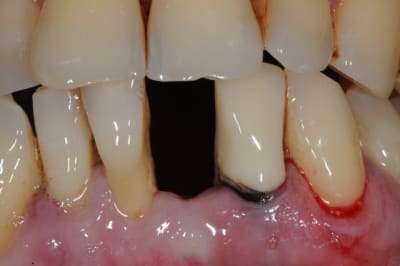

photo 1: début du cas

photo 2: fin d'intervention

photo 3: j+3mois

photo 4 +5: prise d'empreintes

photo 6-7-8-9: couronne finie.

merci de votre attention :)

PS: le patient ne veux pas faire celle d'à coté.

grr, moi ça me démange...

mais tu sais ce que je pense des deux dents voisines...et de l'état paro...

--